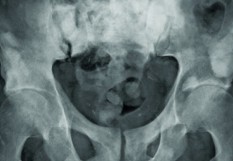

Le dépistage du cancer de la prostate (53 913 nouveaux cas et 8893 décès en 2011 en France métropolitaine selon l’Institut National du Cancer) par dosage annuel du PSA chez tous les hommes âgés de 50 à 75 ans est un sujet de controverses entre partisans convaincus qu’un tel dépistage permet de réduire la mortalité, et opposants considérant que le rapport bénéfice / risque d’un tel screening est défavorable en raison notamment des sur-traitements qu’il induit, avec d’importantes conséquences sur la qualité de vie de patients dont le cancer serait resté latent en l’absence d’intervention thérapeutique.

Cette opposition s’est notamment cristallisée après que deux études aux résultats apparemment discordants ont été publiées il y a quelques années, à savoir la PLCO (Prostate, Lung, Colorectal and Ovarian Cancer Screening Trial) menée aux Etats-Unis et la ERSPC (European Randomized Study of Screening for Prostate Cancer) menée en Europe. L’étude américaine ne montrait pas de bénéfice du screening biologique sur la mortalité quand l’étude européenne mettait en évidence une réduction de la mortalité d’environ 21%. Ce débat connaît une nouvelle avancée puisqu’une étude tout juste publiée dans la revue Annals of Internal Medicine, s’appuyant sur les données des deux études précitées, en arrive à la conclusion que ce screening réduit bel et bien la mortalité imputable au cancer de la prostate. Et cette réduction est loin d’être négligeable puisqu’elle est estimée entre 25 et 31% dans l’étude européenne et entre 27 et 32% dans l’étude américaine. Pourquoi cette nouvelle analyse des résultats de l’étude américaine infirme-t-elle les résultats antérieurs ? Tout simplement en raison d’un biais qui n’avait pas été initialement pris en considération, à savoir que 50% des hommes du groupe contrôle (sans screening) avaient en réalité eu un dosage de PSA antérieurement à la date de leur inclusion dans l’étude, dosage qui avait potentiellement sélectionné un certain nombre de patients à risque soumis en conséquence à un suivi urologique. Le débat autour du PSA n’est sans doute pas clos mais partisans et opposants se retrouveront sans doute autour de positions nouvelles reposant sur les progrès de l’imagerie (IRM) et de la biologie (avec un nouveau marqueur tel que la kallicréine) pour définir de nouvelles procédures permettant de réduire la fréquence des sur-traitements.